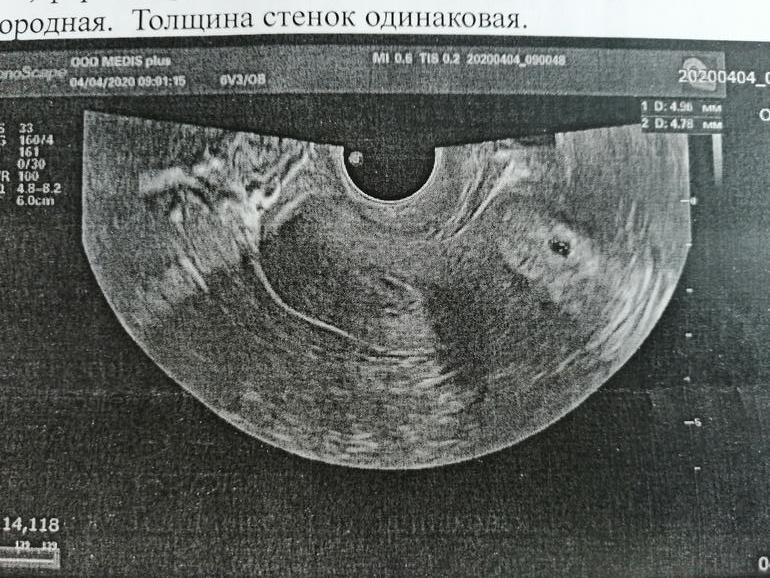

22дпп узи - плодное яйцо в матке

Вот она, моя бусинка! 🥰🥰🥰🥰🥰